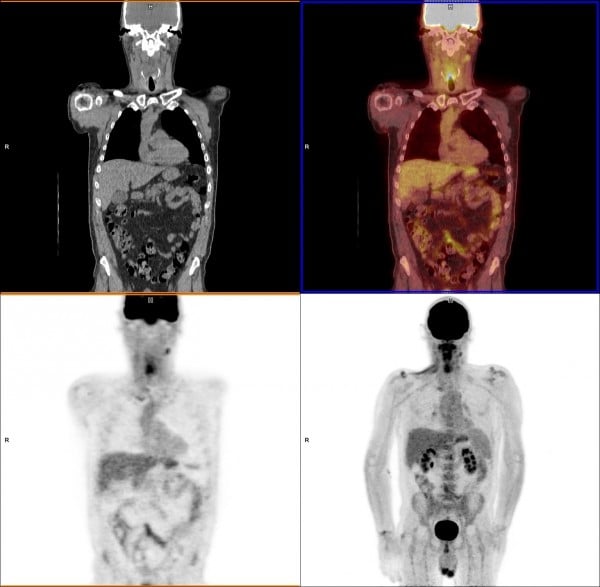

Fdg Pet Scan Identification Of A Primary Lung Carcinoma In A Patient Download Scientific Diagram